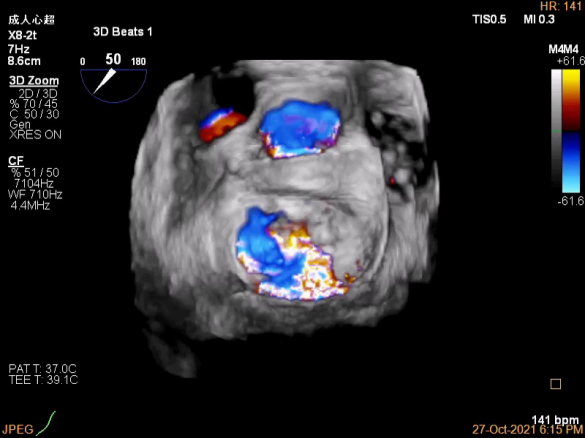

3D视图下观察二尖瓣双孔形态

3D-color:残余少量返流

夹子脱钩后,最终仅少量残余分流